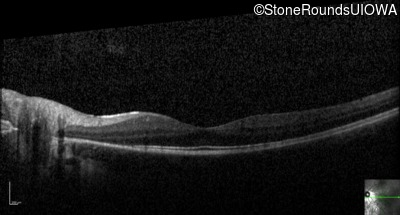

Optical Coherence Tomography - Right - 20/20

Exemplar / OCT Stack

OCT Stack